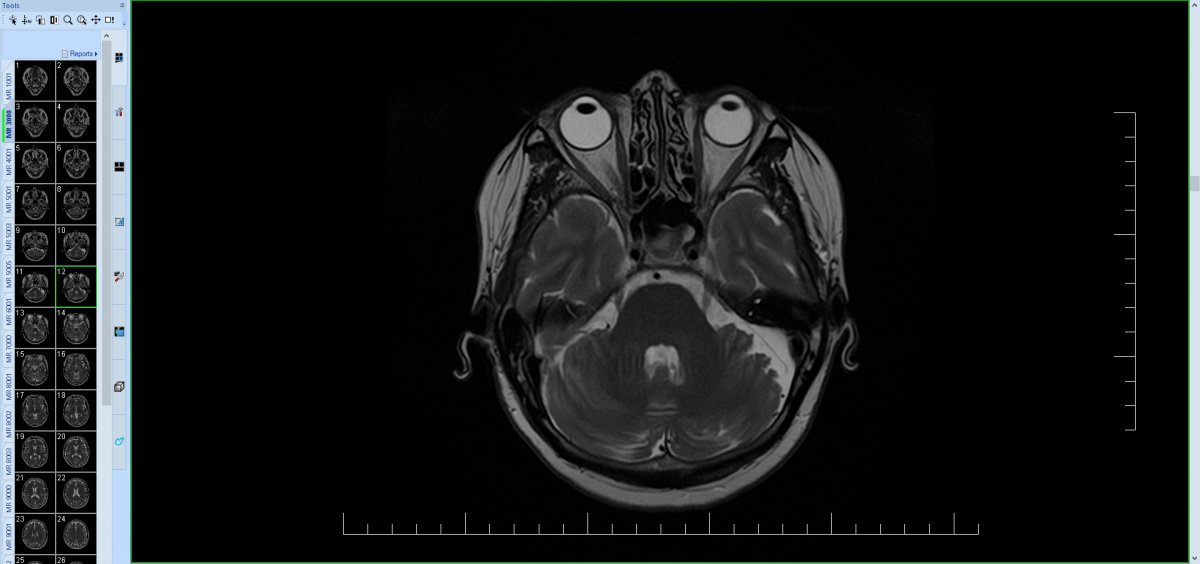

Pacientka nar. 1964 s bolestmi hlavy od r. 2020 s maximem za levým uchem, postupně vyzařování do oblasti tváře, oka, TPM skloubení až do celé levé poloviny hlavy, spíše narůstající intenzita s kolísáním a přechodnými suicidálními verbalizacemi. Od r. 2021 i závratě a zhoršení stability stoje a chůze, bez pádů. Objektivně mírná dystaxie na LHK, chůze a stoj spont. o širší bázi, v BR postojích patrná závislost na zaměření/odklonění pozornosti. Dle MR mozku arachnoidální cysta zadní jámy lební vlevo laterálně vel. 30 x 16 x 26 mm s lehkým tlakem na levou mozečkovou hemisféru, MR AG bez známek neurovaskulárního konfliktu. Konzultováno neurochirurgické pracoviště FN U Sv. Anny v Brně - operační řešení neindikováno, pacientce sděleno, že potíže s nálezem na MR nesouvisí a je třeba hledat jinou příčinu. Doplňována MR C páteře, kde artróza C1/2 a osteochondróza C5/6 s foraminostenózou bilat. více sin., MR TPM skloubení s mírně ventrálnější pozicí disků, vlevo i s mírnou nehomogenitou signálu ve ventrální porci. Pokus o obstřik n. occipitalis major pod UZ kontrolou ve FN bez pozitivního efektu, dle pac. naopak. následně zhoršení obtíží. Vzhledem k susp. psychogenní nástavbě (dlouhodobá konfliktní situace v rodině pacientky) vyšetřena i v amb. pro funkční poruchy a v amb. pro léčbu bolesti, psychoterapii odmítá, na psychiatrii již sledována s dg. somatoformní poruchou, dlouhodobě léčba venlafaxinem + gabapentinem s jen mírným snížením intenzity bolestí, Pregabalin bez efektu, léčebné konopí i léčba opiáty s nežádoucími účinky. Pacientka přesvědčená o souvislosti bolestí s cystou, opakované telefonické konzultace oš. neurologa i několikrát měsíčně pro bolesti, požaduje řešení.

obtíže nesouvisí s arachnoidální cystou, tlakové změny nevidím (škoda, že takto vysloveno), spíše lokální atrofie, nejedná se pravděpodobně o pozůstatek nějakých akutních změn, vrozená. Bez NV konfliktu.